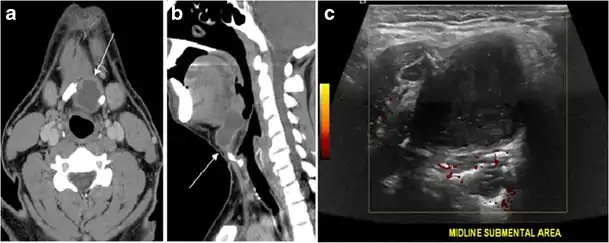

Fig. 13. A 27-year-old female patient known to have goiter. a, b Axial and sagittal enhanced CT scan images of the neck demonstrate a heterogeneously enhancing, enlarged thyroid gland with scattered calcifications (white arrow), cystic changes, and substantial retro-sternal extension (black asterisks). No lymphadenopathy or substantial airway narrowing.[1]

Fig. 14. A 19-year-old male patient known to have multi-nodular goiter and FNA, showing underlying Hashimoto's thyroiditis. a, b Sagittal and transverse greyscale and colour Doppler ultrasound of the neck demonstrate a hypoechoic enlarged right thyroid lobe with small hyperechoic regenerative nodules and marked hypervascularity (white arrows). c, d Enhanced axial CT scan images of the neck demonstrate a heterogeneously enhancing and enlarged thyroid gland, left more than right lobe, and the trachea is markedly narrowed.[1]

Fig. 15. A 33-year-old female patient who presented with neck swelling and pain and was later diagnosed with Hashimoto's thyroiditis. an Axial enhanced CT scan of the neck demonstrates minimal diffuse enlargement of the thyroid gland, especially the isthmus (white arrow). b Transverse greyscale ultrasound of the neck demonstrates heterogeneously enlarged thyroid and thickened isthmus, measuring 8.6 mm.[1]

Malignancy can coexist within the goiter and a CT scan may give a clue if there are abnormal cervical lymph nodes and/or signs of invasion. Retrosternal extension (Fig. 15) could affect the surgical approach, as a lower extent may require a partial or total sternotomy to facilitate complete resection. Therefore, the distance of the retrosternal extent from the sternal notch should be measured on a sagittal image.[1]